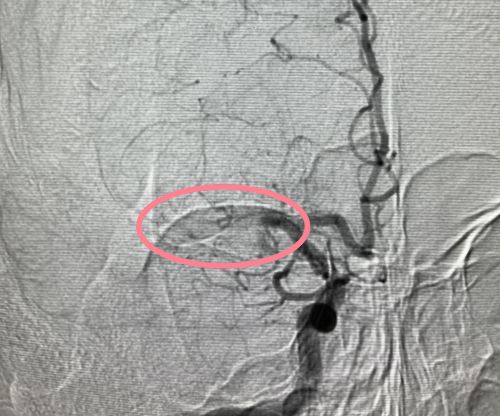

术后,大脑动脉血流恢复。

刘放其副主任医师带领团队立即开启绿色通道,为他紧急施行脑血管造影及脑血管腔内取栓术。

术后,小王语言恢复流利,左侧肢体可以自主抬高。